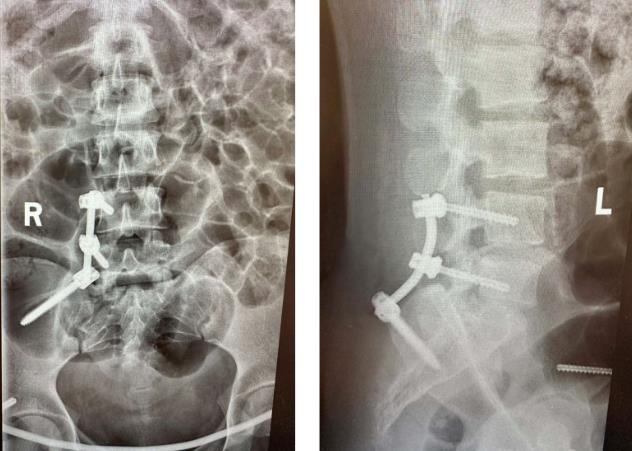

▲术后复查X线

术中,医生采用前后联合入路共切开了3个微小切口,在C形臂X光机透视定位下复位、植入腰髂钉棒+前环钉棒系统,完成了对骨盆骨折的治疗,手术过程顺利。手术对患者的损伤小,组织剥离少,未伤到重要神经、血管,且出血少,术后患者双下肢活动良好,经过一系列的术后护理及康复锻炼,目前已康复出院。